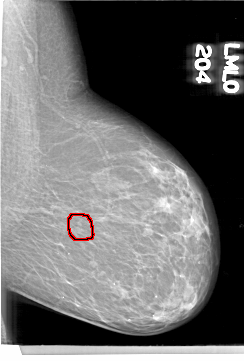

D_4098_1.LEFT_MLO

LEFT_MLO LINES 6841 PIXELS_PER_LINE 4636 BITS_PER_PIXEL 12 RESOLUTION 43.5 OVERLAY

FILE: D_4098_1.LEFT_MLO.OVERLAY

TOTAL_ABNORMALITIES 1

ABNORMALITY 1

LESION_TYPE CALCIFICATION TYPE AMORPHOUS DISTRIBUTION CLUSTERED

ASSESSMENT 0

SUBTLETY 3

PATHOLOGY BENIGN

TOTAL_OUTLINES 1

BOUNDARY